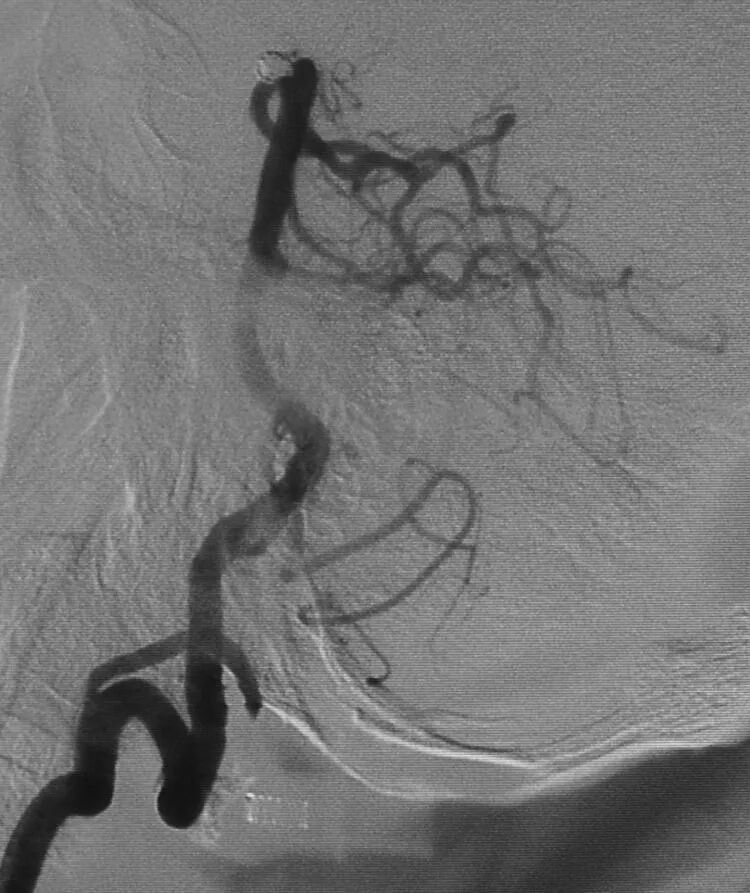

于是我们把微导管头塑成S形

顺利完成该动脉瘤的栓塞。所以,要多角度观察动脉瘤跟载瘤动脉的解剖走行,即使硬件上没有三维工作站,咱们头脑中也要有立体构象,不要一叶障目,被狡猾的敌人所欺骗